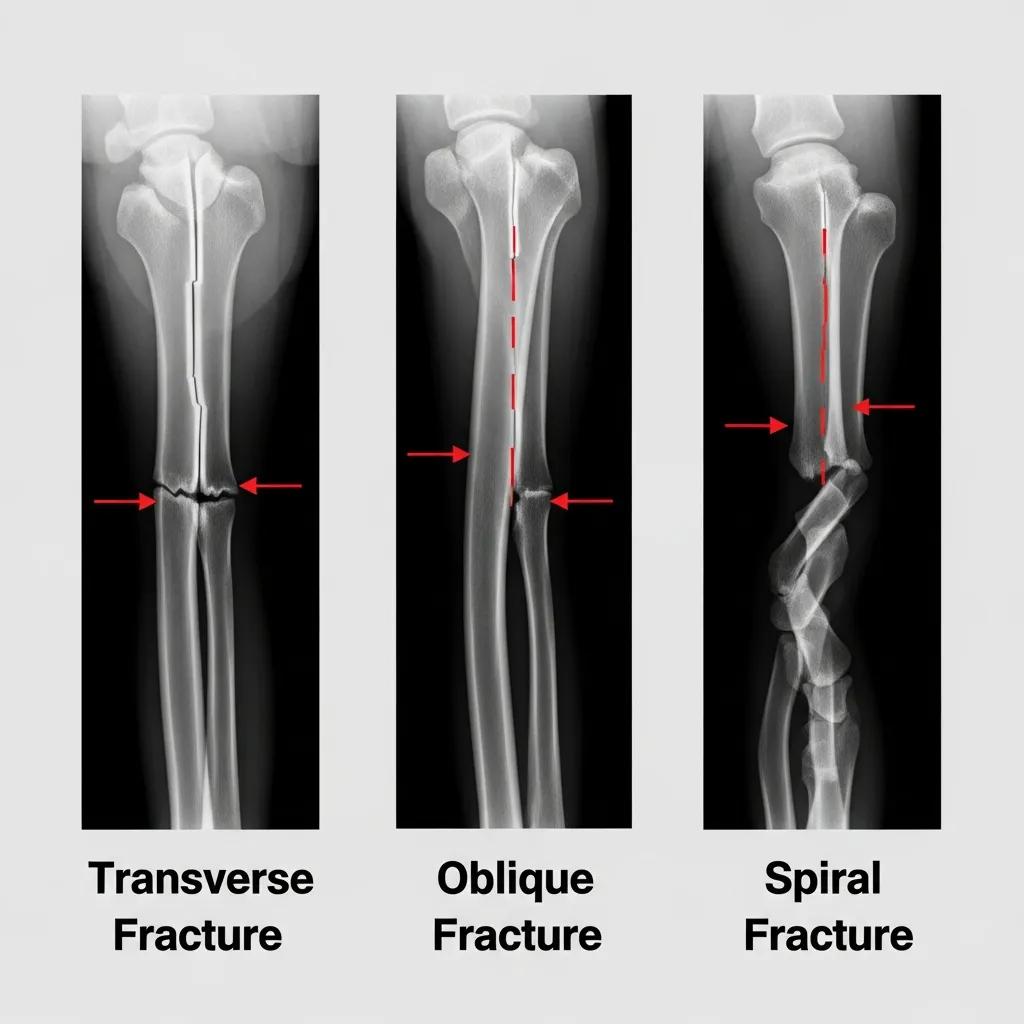

How Do Transverse, Oblique, and Spiral Fractures Appear on Skeletal X-Rays?

Transverse fractures are characterized by a straight break across the bone, often resulting from a direct impact. Oblique fractures, on the other hand, occur at an angle and are typically caused by a twisting force. Spiral fractures are more complex, resulting from a rotational force that causes the bone to break in a spiral pattern. Each type of fracture has a unique appearance on X-rays, which aids in determining the appropriate treatment approach.